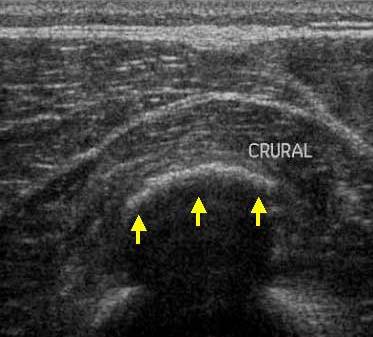

Echivalentul stadiului al III-lea a lui Rodineau se caracterizeaza prin prezenta unei colectii hematice intra sau peri lezionale

Aceasta colectie poate avea o ecostructura lichida sau pseudo-solida, coresponzand unui hematom organizat

Echivalentul stadiului al III-lea a lui Rodineau se caracterizeaza prin prezenta unei colectii hematice intra sau peri lezionale Aceasta colectie poate avea o ecostructura lichida sau pseudo-solida, coresponzand unui hematom organizat In acest caz, doppler-ul este interesant caci permite eliminarea unei formatiuni tisulare vascularizate care constituie principalul diagnostic diferential.